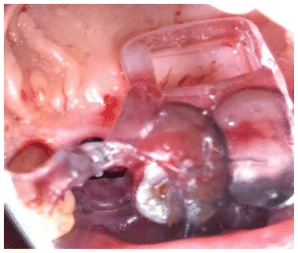

- The block graft was trimmed extra orally. (Figure 7)

- The block was then fixed in place with 2 screws.

- The rest of the cyst defect was grafted with a mixture of auto (scraped with a bone scrapper) and xenograft (cerabone®, Botiss Biomaterials GmbH, Germany) (Figure 8)

- A collagen membrane was sutured in place OSSIX-Plus (OraPharma Inc., Warminster, Pennsylvania).